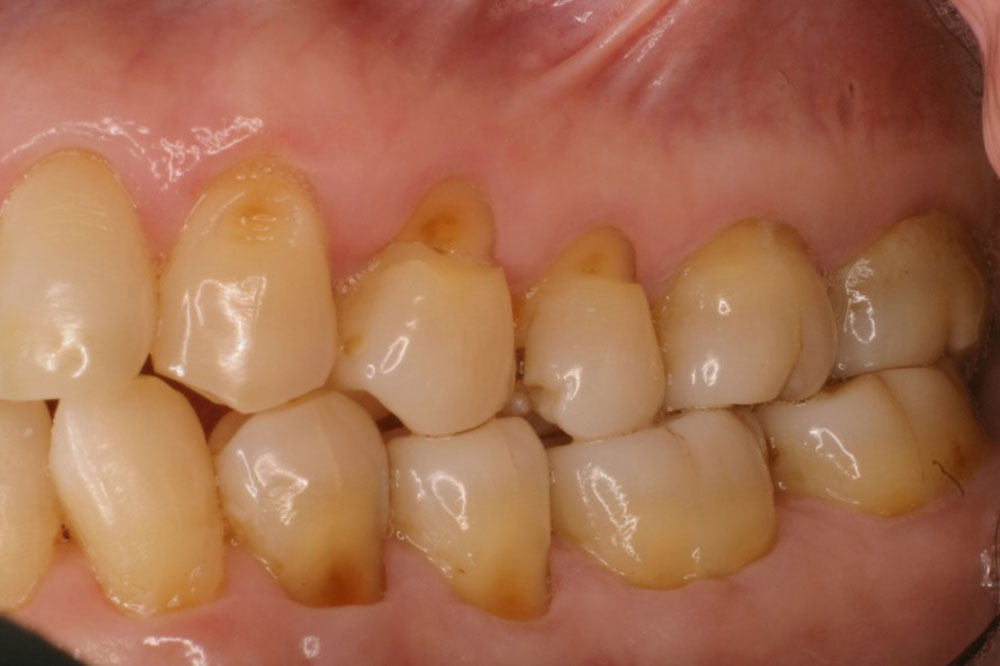

3-7.歯周病の悪化

歯周病の悪化

歯周病は骨の支えがなくなってしまっている状態です。

支えが少なくなっている歯に、歯ぎしりの力が加わることによって、更に骨の支えが減っていってしまいます。